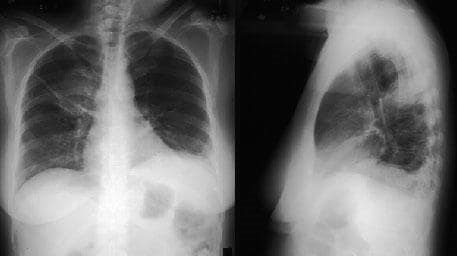

Инфильтрация Легких Фото